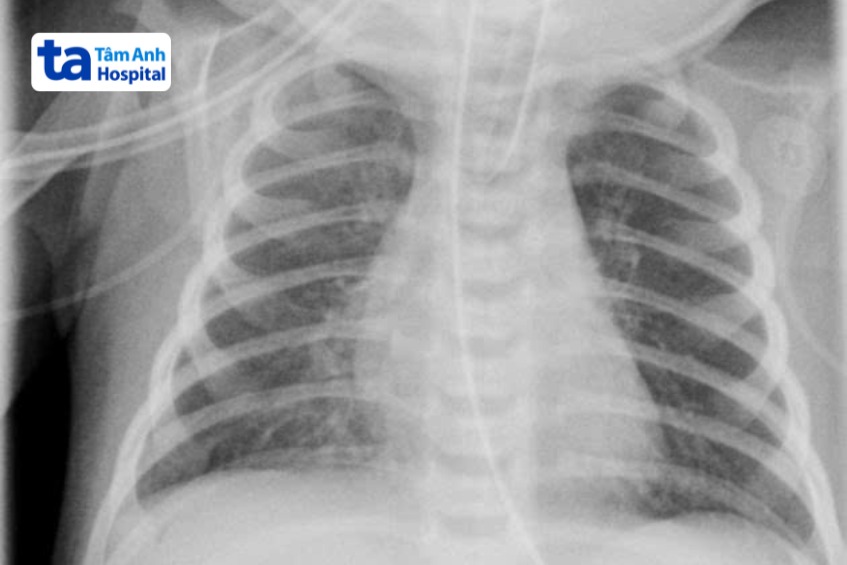

Khi nghi ngờ nhiễm trùng huyết, bác sĩ sẽ khám lâm sàng và thực hiện một số cận lâm sàng để kiểm tra tình trạng sức khỏe của trẻ. Các cận lâm sàng có thể được chỉ định trong chẩn đoán viêm phổi sơ sinh: